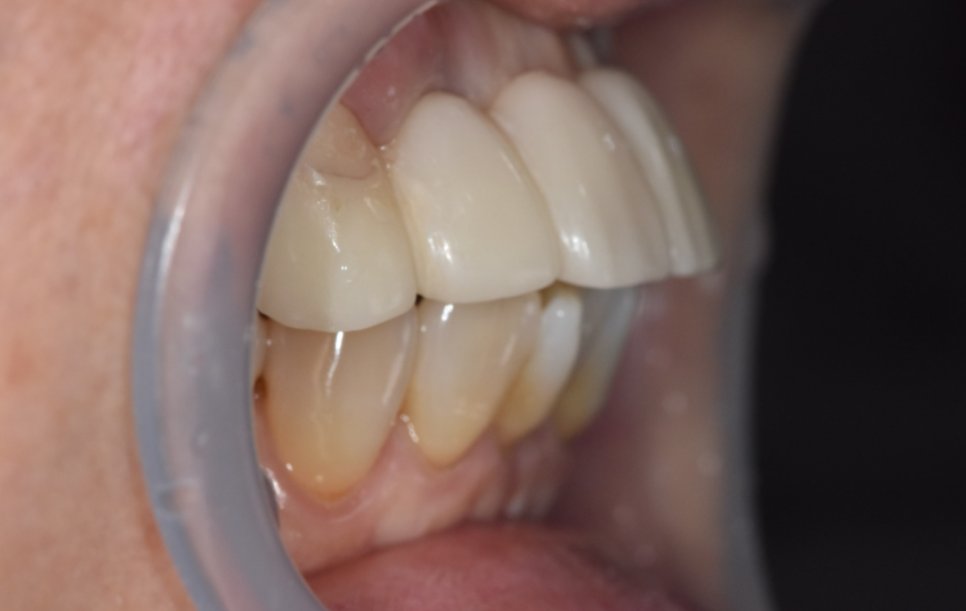

양쪽 송곳니를 살짝 다듬어야 하는데,

여기서 고민이 생겼어요.

송곳니는 신경이 살아있는 치아라 너무 많이 깎으면 시릴 수 있습니다.

그래서 최소한만 삭제했는데,

이렇게 하면 다른 문제가 생깁니다.

환자분 아래 앞니도 원래 약간 앞으로 나와 있는 편이셨어요.

위 치아가 아래 치아를 덮는 구조인데,

삭제량이 적으면 위 치아가 더 나와 보일 수 있습니다.

임시치아, 옆 위아래 모두 확인하여 조정

이 임시치아로 환자분과 크기나 모양에 대한 의견을 나눕니다.

기공소가 병원 안에 있으니까 환자분의 의견을 바로바로 반영 가능.

"이 모양 어떠세요? 크기는 괜찮으세요?"

"조금만 더 작게 해주실 수 있을까요?"

하나하나 반영해서 다시 만들고, 또 확인받고.

이 과정을 여러 번 반복했습니다.